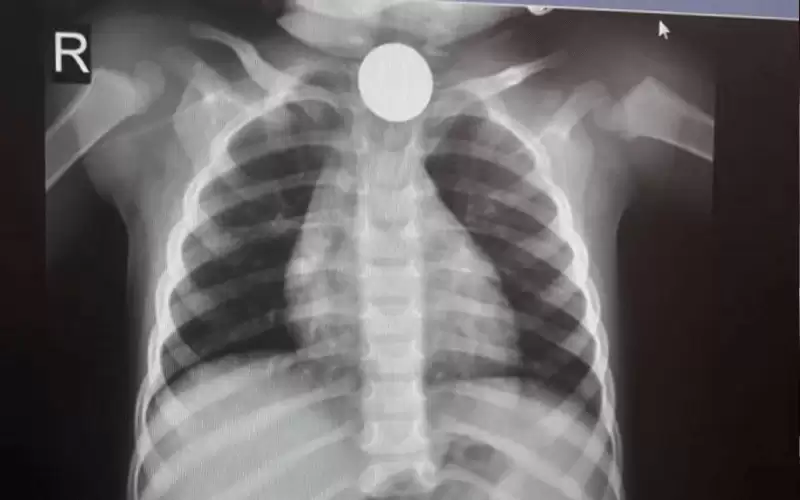

اسعاف طفل ابتلع 'بريزة' في عمان